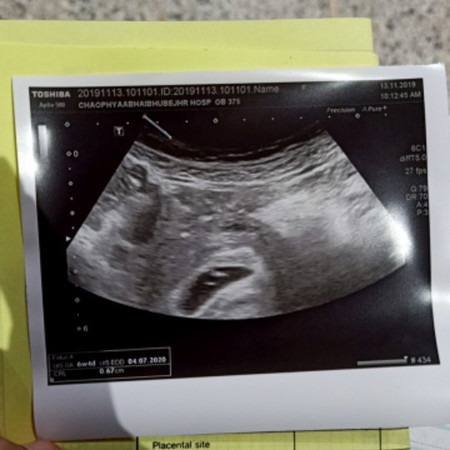

จุดสีขาว2จุดคืออะไรคะ

มีใครอัลตร้าซาวด์แล้วเห็นแบบเราหรือป่าวคะ

กี่วีคแล้วค่ะ อาจจะเป็นถุงไข่แดงค่ะ